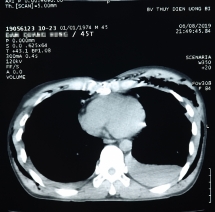

Cứu sống bệnh nhân gãy 15 xương sườn, tràn khí màng phổi

Khi đang làm việc bị đất đổ đè vào lưng, người bệnh bị gãy nhiều xương sườn, gãy xương đòn phải, xương bả vai phải và tràn máu, tràn khí màng phổi 2 bên.